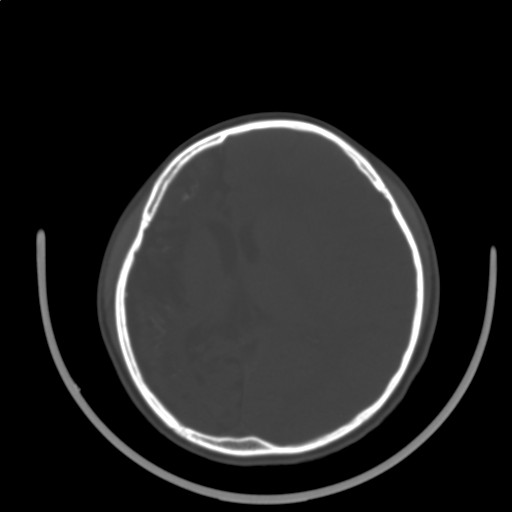

标题: PED3416:F,12Y,智力下降,学习成绩差,8个月时发过高烧。

右侧半球萎缩,软化,多量脑回样钙化,考虑颅面血管瘤病,建议dsa检查

右侧半球萎缩,软化,多量脑回样钙化,同侧颅盖板障增宽,考虑颅面血管瘤病,建议dsa检查与化脓性脑膜炎后遗改变鉴别。